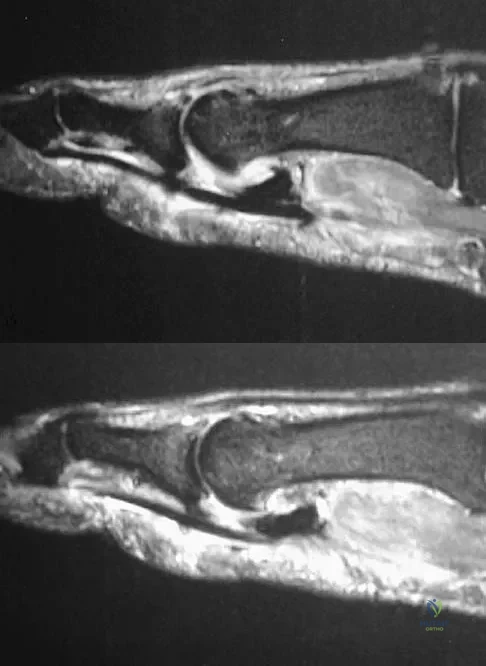

A patient notes pain under the first metatarsophalangeal joint following a soccer injury. The MRI scans shown in Figures 27a and 27b reveal what pathologic finding?

Explanation